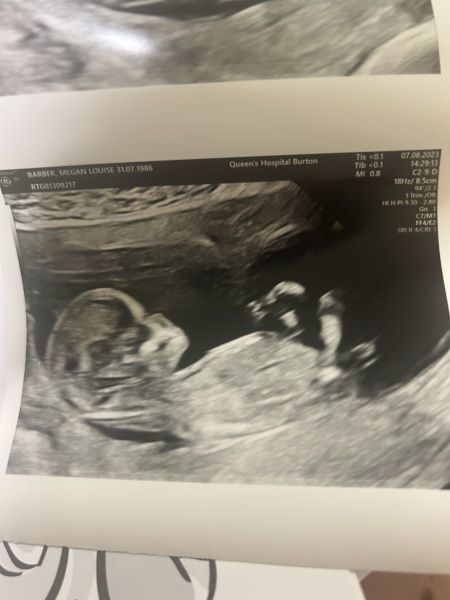

little update ladies.. just had my 12 week scan and my god do I have an active bean 🫘. They were wild which was lovely to see. Measuring at 12 +2 which is due date 17th of Feb.

will send the pic now as well :)

@MeganBistram that is the most gorgeous photo 😍😍 ahhh it makes me so happy. Thank yous o much for sharing. I hope you start enjoying the whole pregnancy from now on. Wish you all the luck ❤️❤️❤️

lovely scan photo. I’m a February baby 🥰Just be careful you’re name dob is in the photo…just thinking of scammers etc xx

@MeganBistram that photo made my eyes instantly well up!!! I’m SO happy for you!! Almost a valentines baby!! ❤️❤️❤️ How perfect and so so exciting.

@MeganBistram that is absolutely wonderful, massive congratulations! Delighted for you. This gives us all so much hope!! Are you feeling like you can relax now?